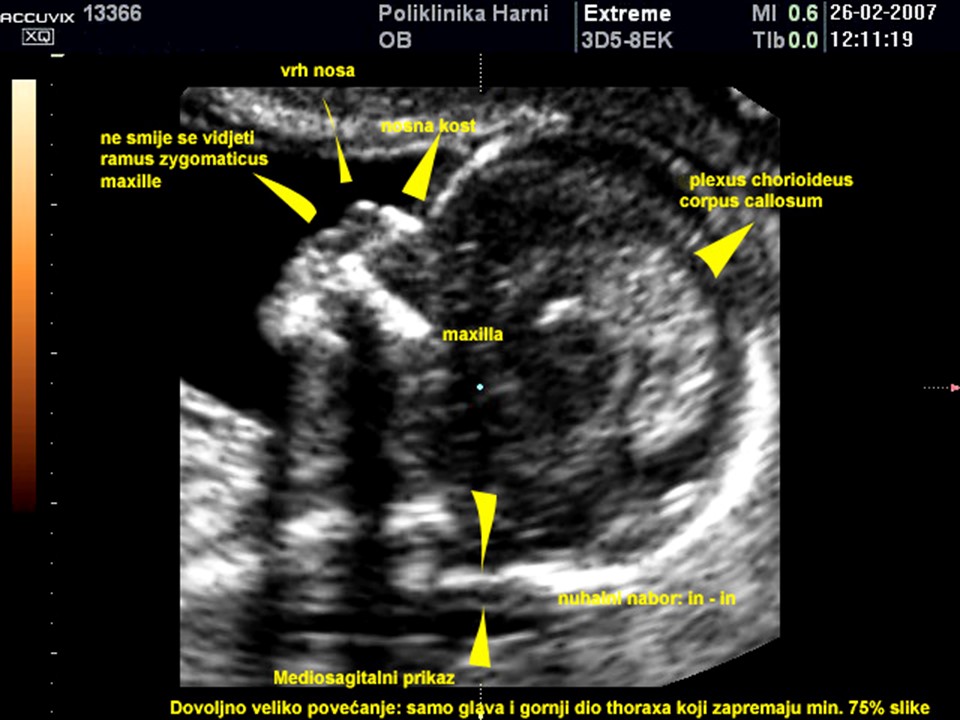

Radi se o specifičnim ultrazvučnim pokazateljima koji ne spadaju u anomalije već prije prolazne pojave u trudnoći. Obuhvaćaju ne samo debljinu nuhalnog nabora, već i prisutnost nosne kosti, lični kut, nalaz dvije umbilikalne arterije, procjenu protoka kroz duktus venozus tijekom atrijske kontrakcije i nalaz trikuspidalne regurgitacije. Procjenjuju se prema strogim kriterijima koje je propisao FMF – Fetal Medicine Foundation, London, između 11. i 13+6 tjedna trudnoće kada je duljina tjeme-trtica između 45 - 84 mm. Ovaj ultrazvučni pregled je poznat i pod nazivom mini-anomaly scan.

Preduvjet za mjerenje nuhalnog nabora i primjenu ostalih ultrazvučnih biljega u razvrstavanju trudnica po skupinama rizika temeljem računalnog programa je stjecanje licencije i redovita godišnja certifikacija u okviru Fetal Medicine Foundation London. Poliklinika Harni je prva zdravstvena ustanova u Hrvatskoj, certificirana od strane Fetal Medicine Foundation London za provođenje kombiniranog probira za kromosomske abnormalnosti.